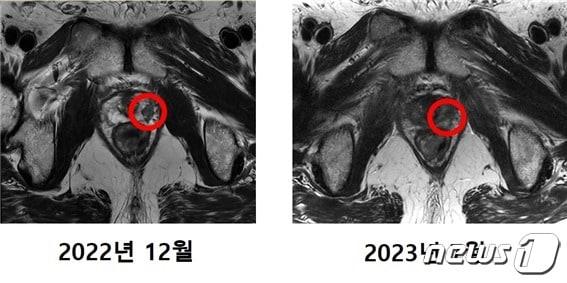

본문 이미지 - 중입자 치료를 받은 최 모 씨(64)의 MRI 촬영 사진. 기존에 발견됐던 암 조직(왼쪽 사진 표시)이 치료 후에는 발견되지 않았다. (연세암병원 제공)

중입자 치료를 받은 최 모 씨(64)의 MRI 촬영 사진. 기존에 발견됐던 암 조직(왼쪽 사진 표시)이 치료 후에는 발견되지 않았다. (연세암병원 제공)